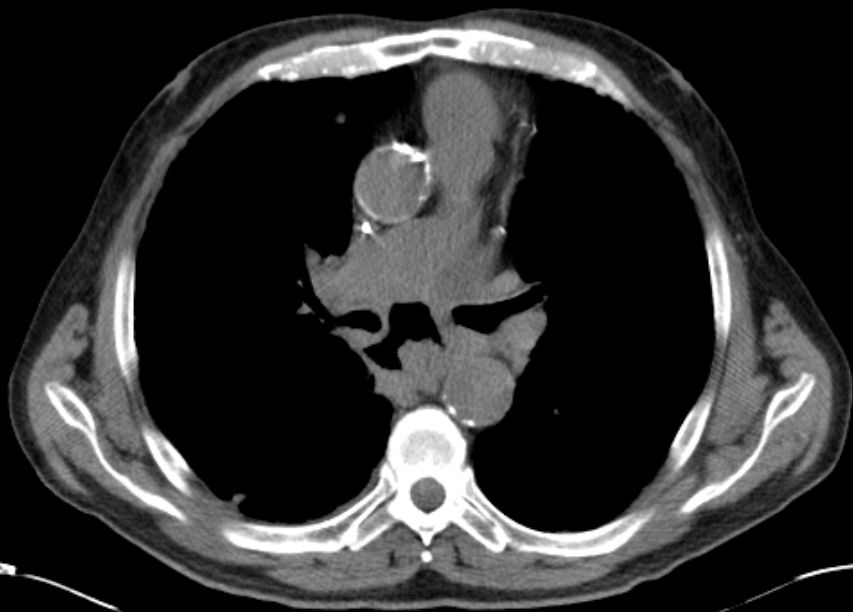

CT Infiltration des oberen Mediastinums. Flottierender Thrombus in der Vena cava superior.